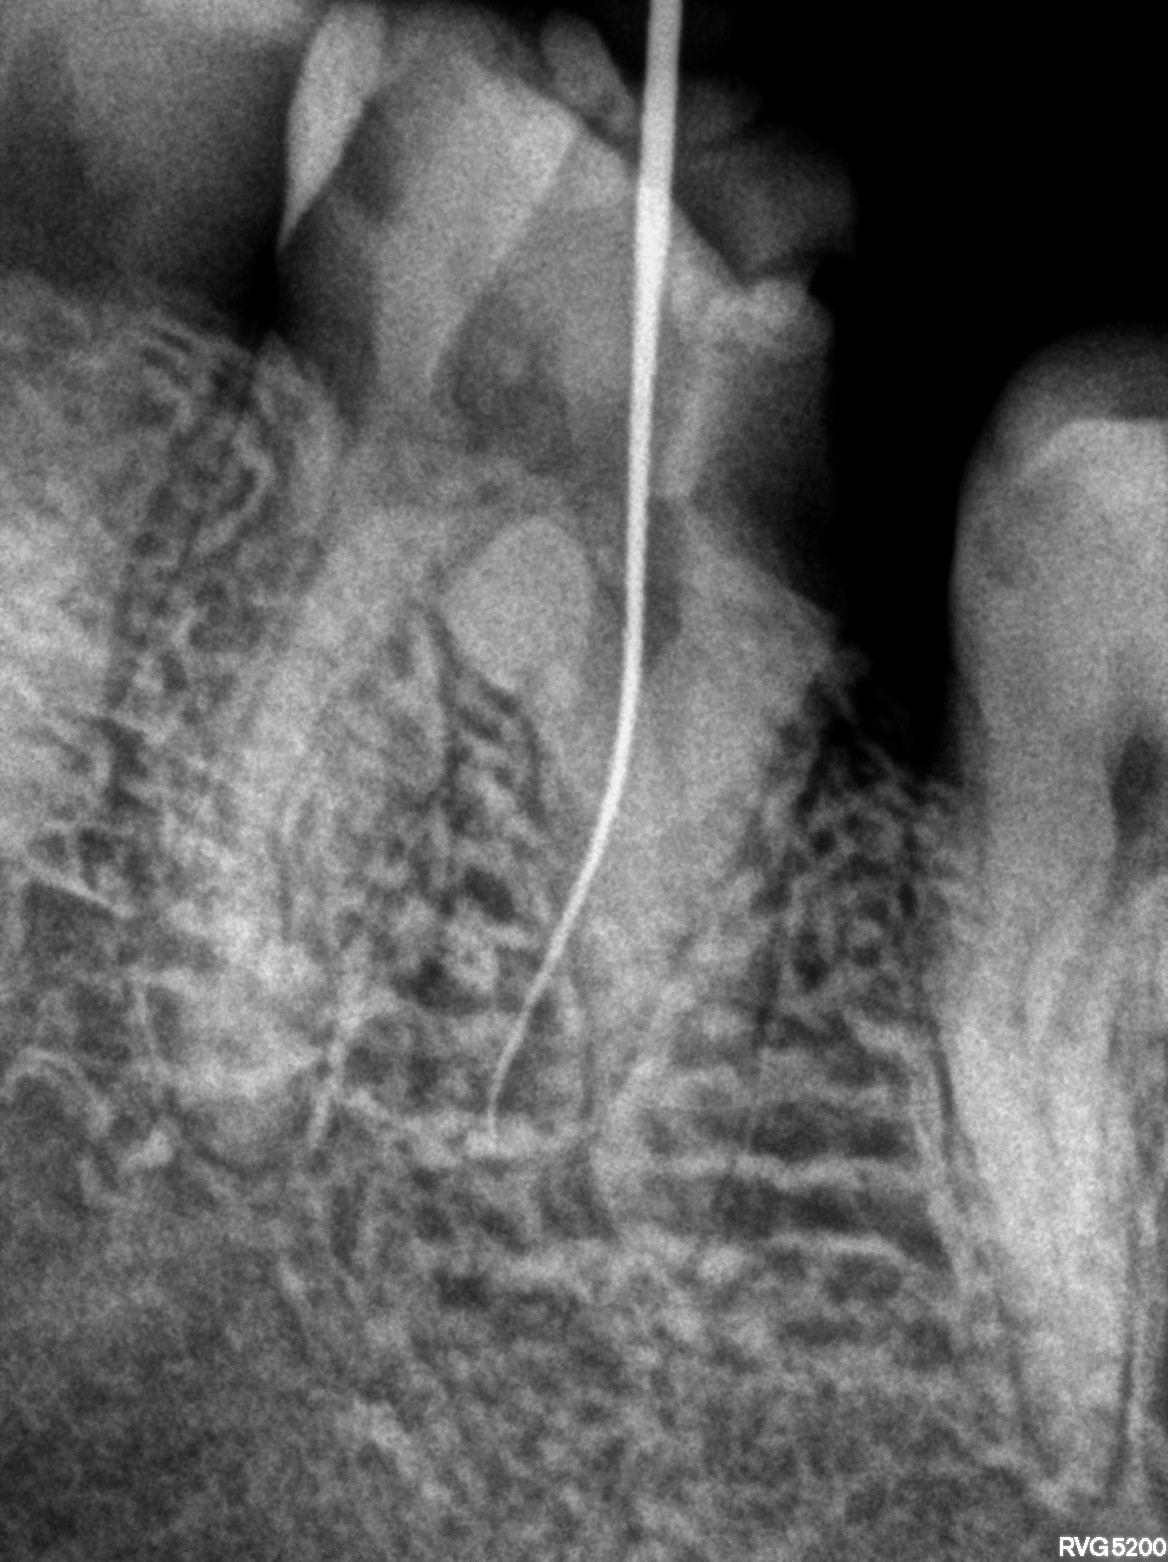

Dental Radiographs FHIR: DocumentReference · LOINC 24641-7

xray_1772642477_1.jpg

24641-7